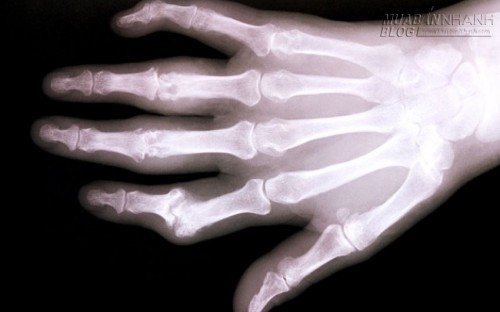

Xương có thể được tái sinh để hỗ trợ cho người bị bệnh loãng xương.